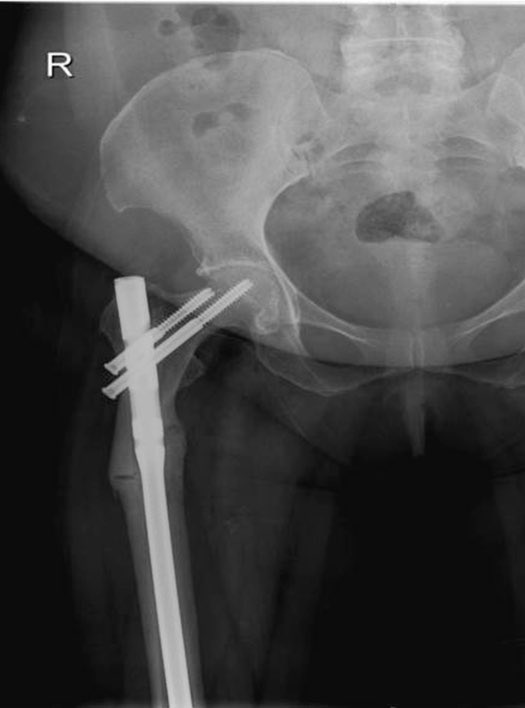

تعتبر كسور العمود الفقري أو الورك الناتجة عن هشاشة العظام من أكبر وأشد المضاعفات التي قد تؤدي إلى إعاقات أو خطر الوفاة لا قدر الله خصوصا في العام الأول من الإصابة كما أثبتت بعض الأبحاث.

مضاعفاته:قد يسبب تنخر العظم في الفك أو حدوث كسر غير عادي في أعلى عظمة الفخذ.

الخلاصة:ينبغي أخذ أدوية الهشاشه في حال وجودها والمضاعفات التي ذكرتها نادرة والفائدة تفوق تركها.في حال حدوث كسر غير عادي في عظمة الفخذ يلجأ الجراح إلى إيقاف البييفوسوفيت فورا وسيقوم بتثبيت عظمة الفخذ سواءا كان الكسر كامل أو جزئي.